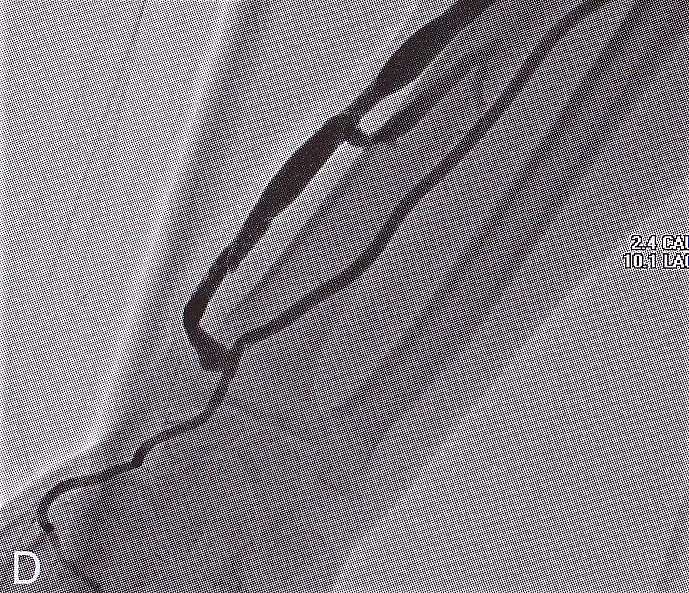

Circuit VesperⅡは、シャントPTAを中心とした教育・トレーニングおよびカテーテル評価を目的としたシミュレーターです。

Circuit VesperⅡは、高透明度シリコン樹脂による一体成型を採用しています。

熟練職人の技術が細部にまで反映され、精巧かつ高品質なモデルを実現しました。

シャントPTA手技の全体像を立体的に観察できることにより、想定外の学習効果や、カテーテル性能の総合的な評価にもつながります。